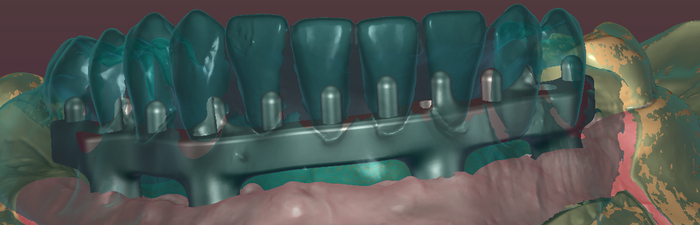

С восковой постановки зубов снимается "ключ" с помощью которого зубы переносятся на каркас.

Далее проверяю если не нарушилось положение зубов при переносе, моделирую форму десны будущих протезов, снимаю при помощи технического силикона формы в которые заливается пластмасса.

верхний протез – временный, по этому у него изначально смоделирована десна. Нижний – постоянный. На него буду наносить фотополимерный композит, схожий или такой-же как и пломбировочный материал.